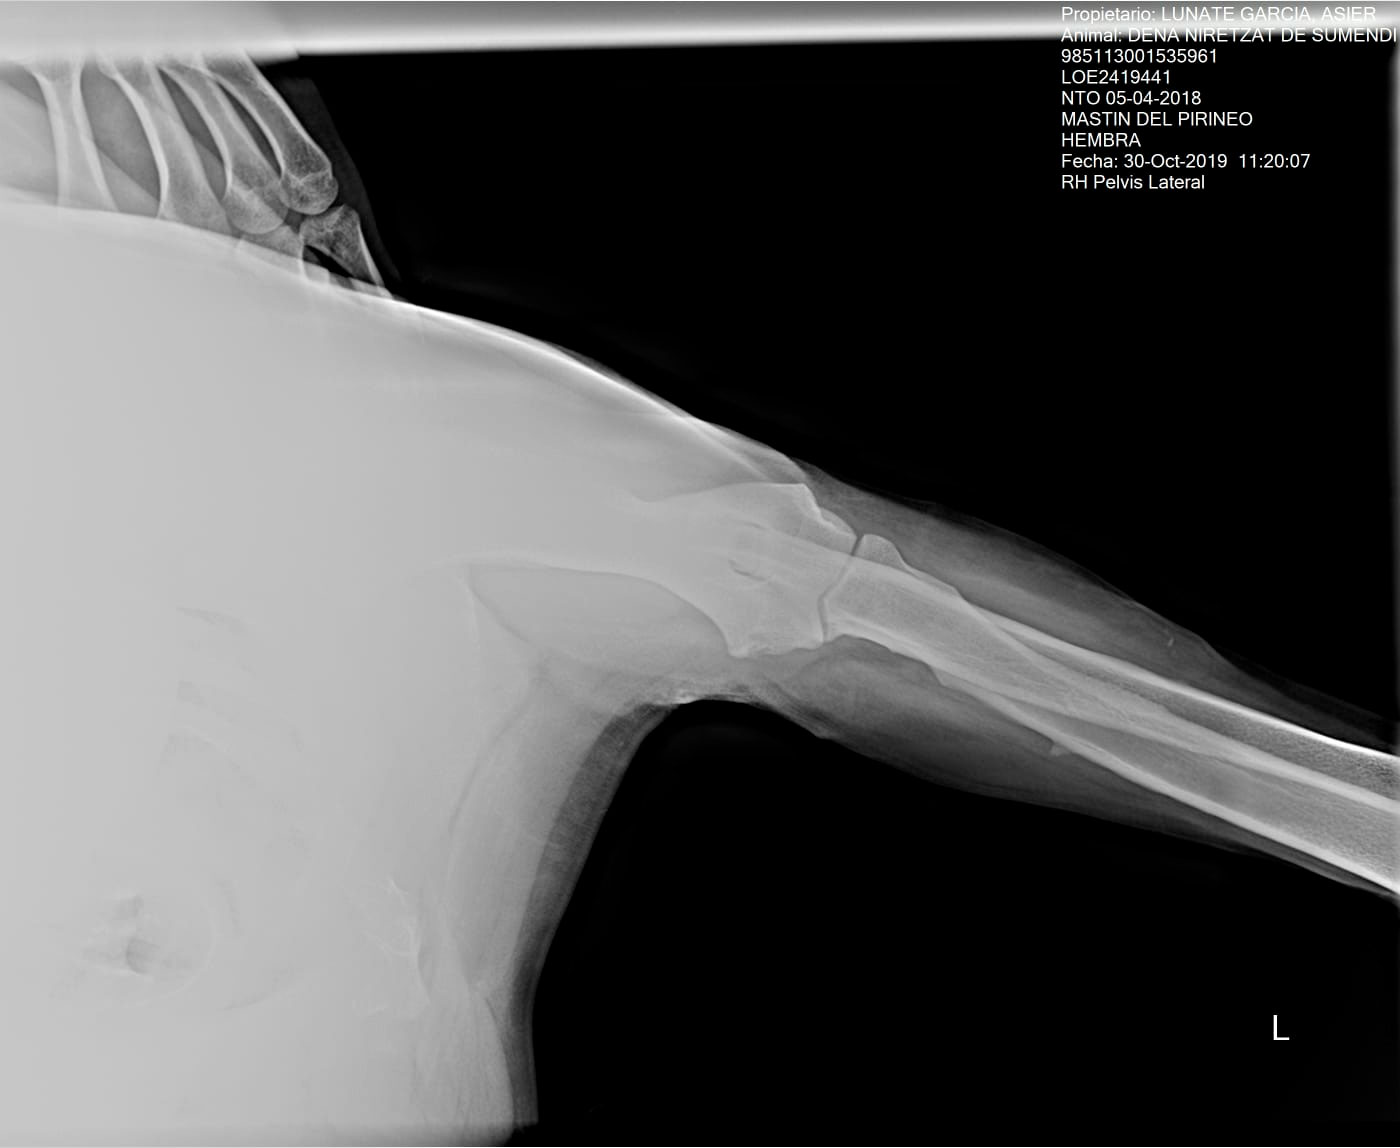

DENA NIRETZAT DE SUMENDI